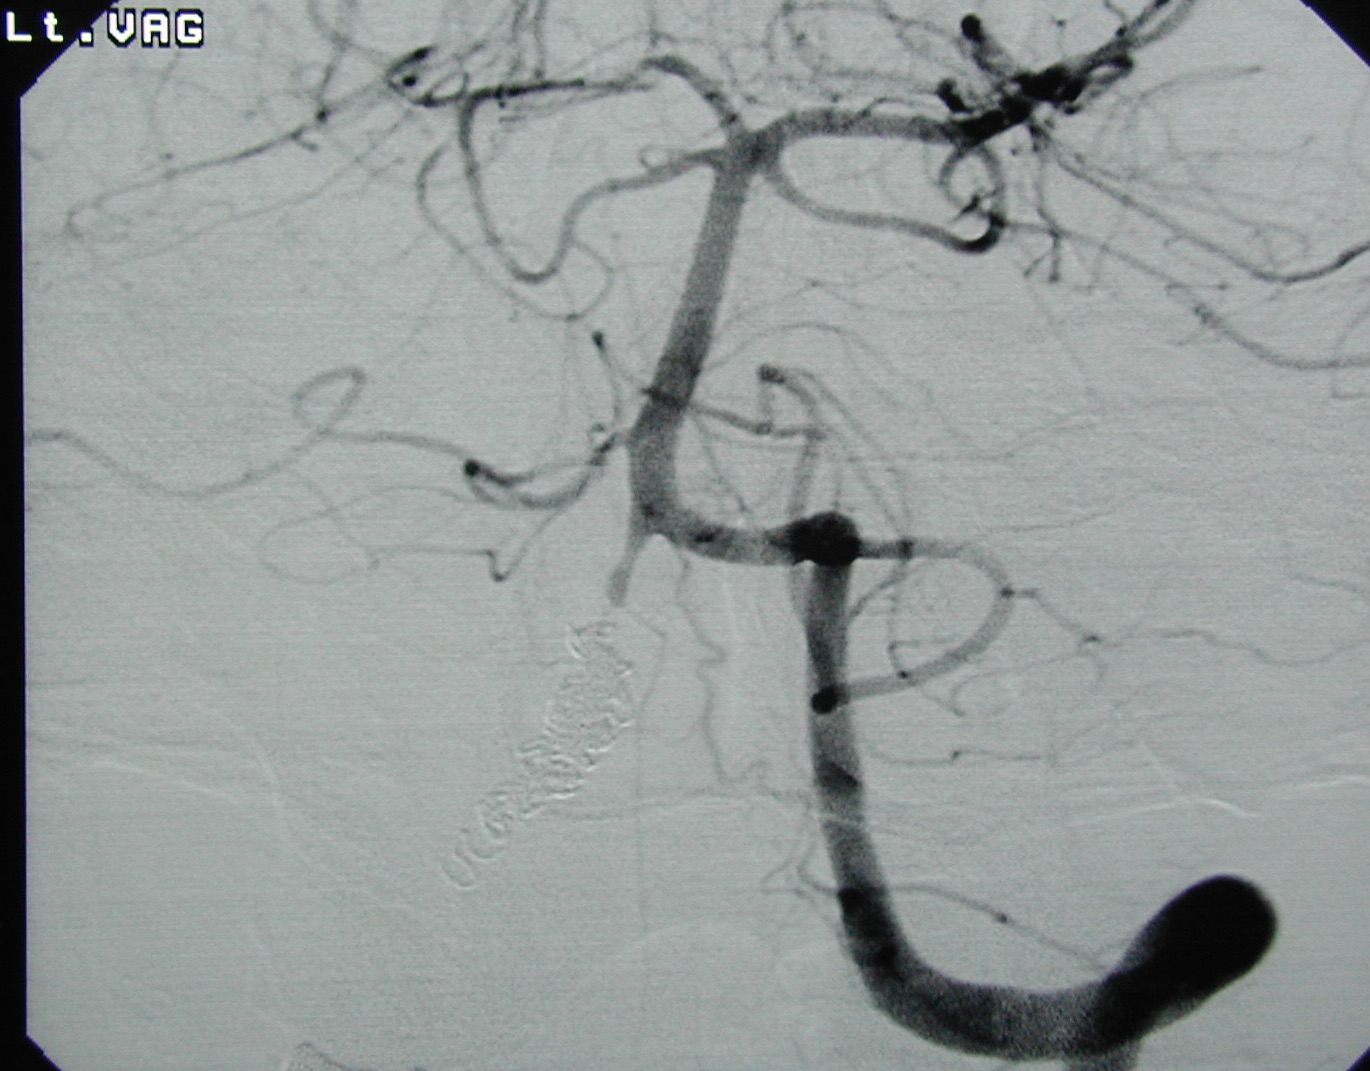

<コイル塞栓術後:右椎骨動脈を動脈瘤ごとコイルで閉塞>

<コイル:矢印>

<左椎骨動脈撮影:右椎骨動脈と動脈瘤は写らなくなった(治癒)>